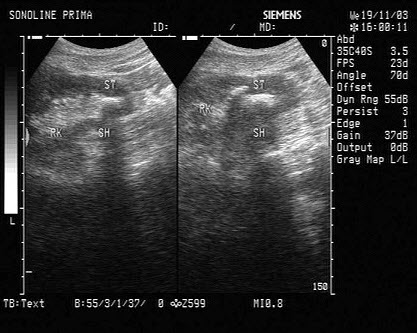

257、单项选择题 哪一类扫查可以显示以上肾脏图形()

A.横向扫查

B.经肝纵向扫查

C.肋缘下斜行扫查

D.背部纵向扫查

E.经侧腰部冠状扫查